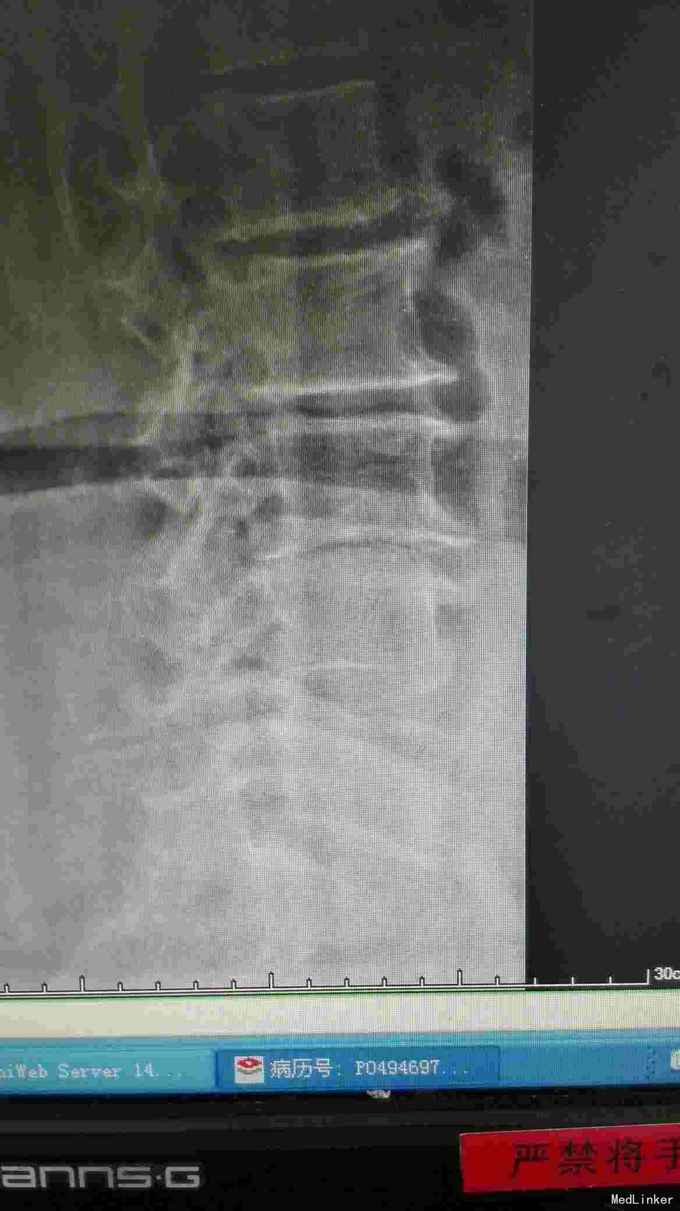

腰椎影像检查提示椎间盘突出,椎管狭窄,退变侧弯。

诊断腰椎间盘突出症,腰椎管狭窄症,腰椎退变性侧弯。 在全麻下行腰椎固定,减压,畸形矫正融合术。